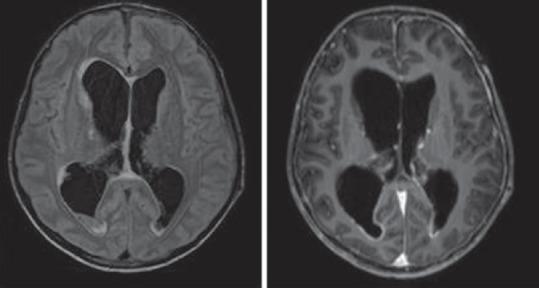

快速进展性认知衰退综合征——我们的经验

Syndromes of Rapidly Progressive Cognitive Decline-Our Experience.

RESULTS AND CONCLUSIONS

Out of 144 patients 42 had immune-mediated encephalopathy, 18 had Creutzfeldt-Jakob disease, 3 had Vitamin B12 deficiency, 63 had infection with neurocysticercosis, 7 had tuberculosis, 2 had HIV, 1 had herpes simplex encephalitis, 1 had neurosyphilis, 1 Whipples disease, 1 had Subacute Sclerosing Panencephalitis, 1 had Mass lesion, 3 had Frontotemporal dementia, and 3 had small vessel disease. Good majority of these patients have infective and immune-mediated causes and less number belong to degenerative group. Therefore, caution is needed to look for treatable cause as it carries a different treatment options and outcome.

结果与结论

144例患者中,42例患有免疫介导性脑病,18例患有克雅氏病,3例患有维生素B12缺乏症,63例患有神经囊尾蚴病感染,7例患有结核病,2例患有艾滋病,1例患有单纯疱疹性脑炎,1例患有神经梅毒,1例患有惠普尔病,1例患有亚急性硬化性全脑炎,1例患有占位性病变,3例患有额颞叶痴呆,3例患有小血管疾病。这些患者中绝大多数有感染性和免疫介导性病因,属于退行性病变组的较少。因此,需要谨慎寻找可治疗的病因,因为其治疗选择和结果不同。